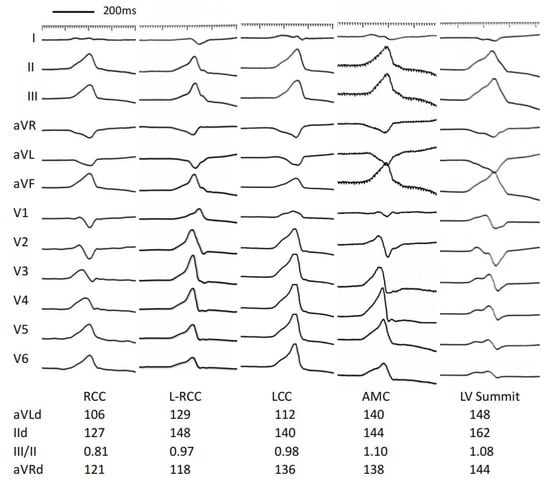

| Total QRS duration (ms) | 150 ± 28 | 142 ± 15 | 147 ± 13 | 158 ± 13 # | 178 ± 26 *#&$ |

| Lead II | 132 ± 13 | 134 ± 16 | 142 ± 14 | 152 ± 11 *# | 171 ± 30 *#&$ |

| Lead III | 131 ± 11 | 129 ± 19 | 139 ± 16 | 152 ± 11 *# | 169 ± 34 *#& |

| Lead aVF | 130 ± 10 | 133 ± 17 | 141 ± 16 | 151 ± 11 *# | 168 ± 30 *#& |

| Lead aVL | 113 ± 19 | 124 ± 18 | 130 ± 17 * | 147 ± 13 *#& | 153 ± 24 *#& |

| Lead aVR | 125 ± 14 | 128 ± 14 | 139 ± 15 *# | 146 ± 14 *# | 155 ± 15 *#& |

| The ratio of III/II | 0.78 ± 0.15 | 0.94 ± 0.16* | 1.03 ± 0.13 * | 1.10 ± 0.16 *# | 1.06 ± 0.10 * |

| The ratio of aVL/aVR | 0.58 ± 0.28 | 1.12 ± 0.36 * | 1.20 ± 0.36 * | 1.45 ± 0.38 *# | 1.18 ± 0.18 * |